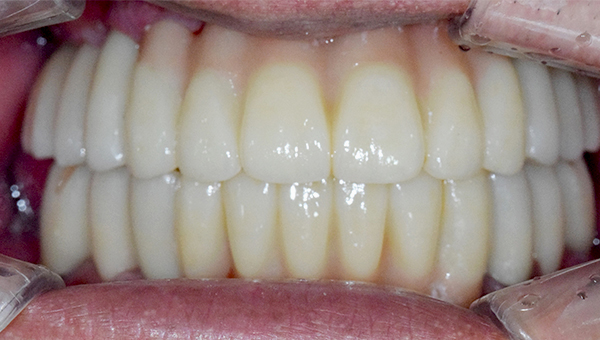

강*란 임플란트 시술 사례

전체 임플란트

2025.02.07

치료 전

2025.08.19

치료 후